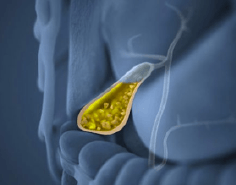

Vesícula Biliar

La cirugía de la vesícula biliar, llamada Colecistectomía Laparoscópica, es el procedimiento por el cual se lleva a cabo la extirpación de la vesícula. Este tipo de cirugía está indicada cuando la vesícula biliar contiene litos o piedras en su interior causando un proceso inflamatorio agudo o crónico llamado Colecistitis Litiásica. Los síntomas dependerán si se presenta el cuadro clínico de manera crónica con dolor abdominal de larga evolución en región subcostal derecha, nausea, vómito o si los síntomas se presentan de manera súbita con dolor abdominal de gran intensidad requiriendo de manejo quirúrgico de urgencia.

La cirugía se realiza mediante laparoscopía a través de 3 pequeñas incisiones de 5 y 10 mm, extrayéndose la vesícula por una de estas heridas, lo cual permite excelentes resultados estéticos, una pronta recuperación con mínimo dolor y una rápida reintegración a sus actividades. A pesar de que es un padecimiento frecuente, se requiere amplia experiencia para evitar complicaciones o lesiones desencadenadas durante la cirugía, es por ello que ofrecemos una atención de alta calidad, con el mejor equipo médico y técnico para poder resolver esta patología con la menor probabilidad de riesgos o complicaciones y con una recuperación prácticamente inmediata.